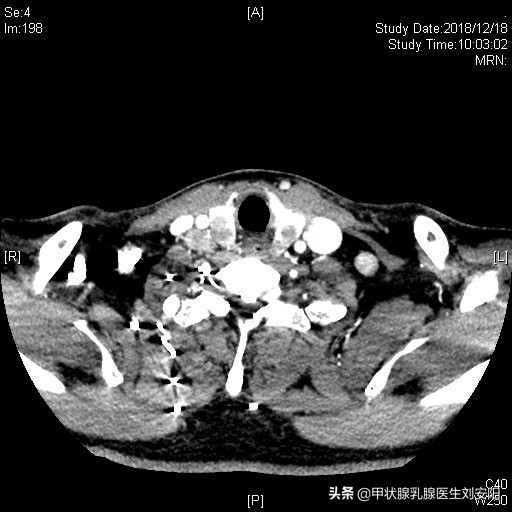

颈部增强CT:双侧甲状腺肿瘤,未见累积气管,中央区及双侧II/III/IV区多发肿大淋巴结,有强化。如图。